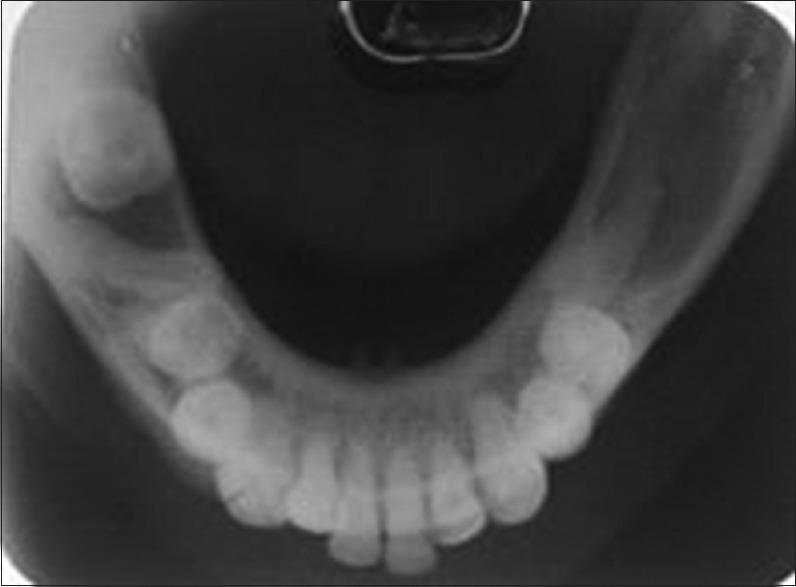

Odontogenic keratocyst(OKC)is a cyst oftooth origin with an aggressive behavior including a high recurrence rate, it has been rechristened to keratocystic odontogenic tumor(KCOT) as it be the reflects its neoplastic nature. We report a case of KCOT in association with an impacted supernumerary tooth along with Trigeminal Neuralgia, that subsided by itself after removal of the cyst.